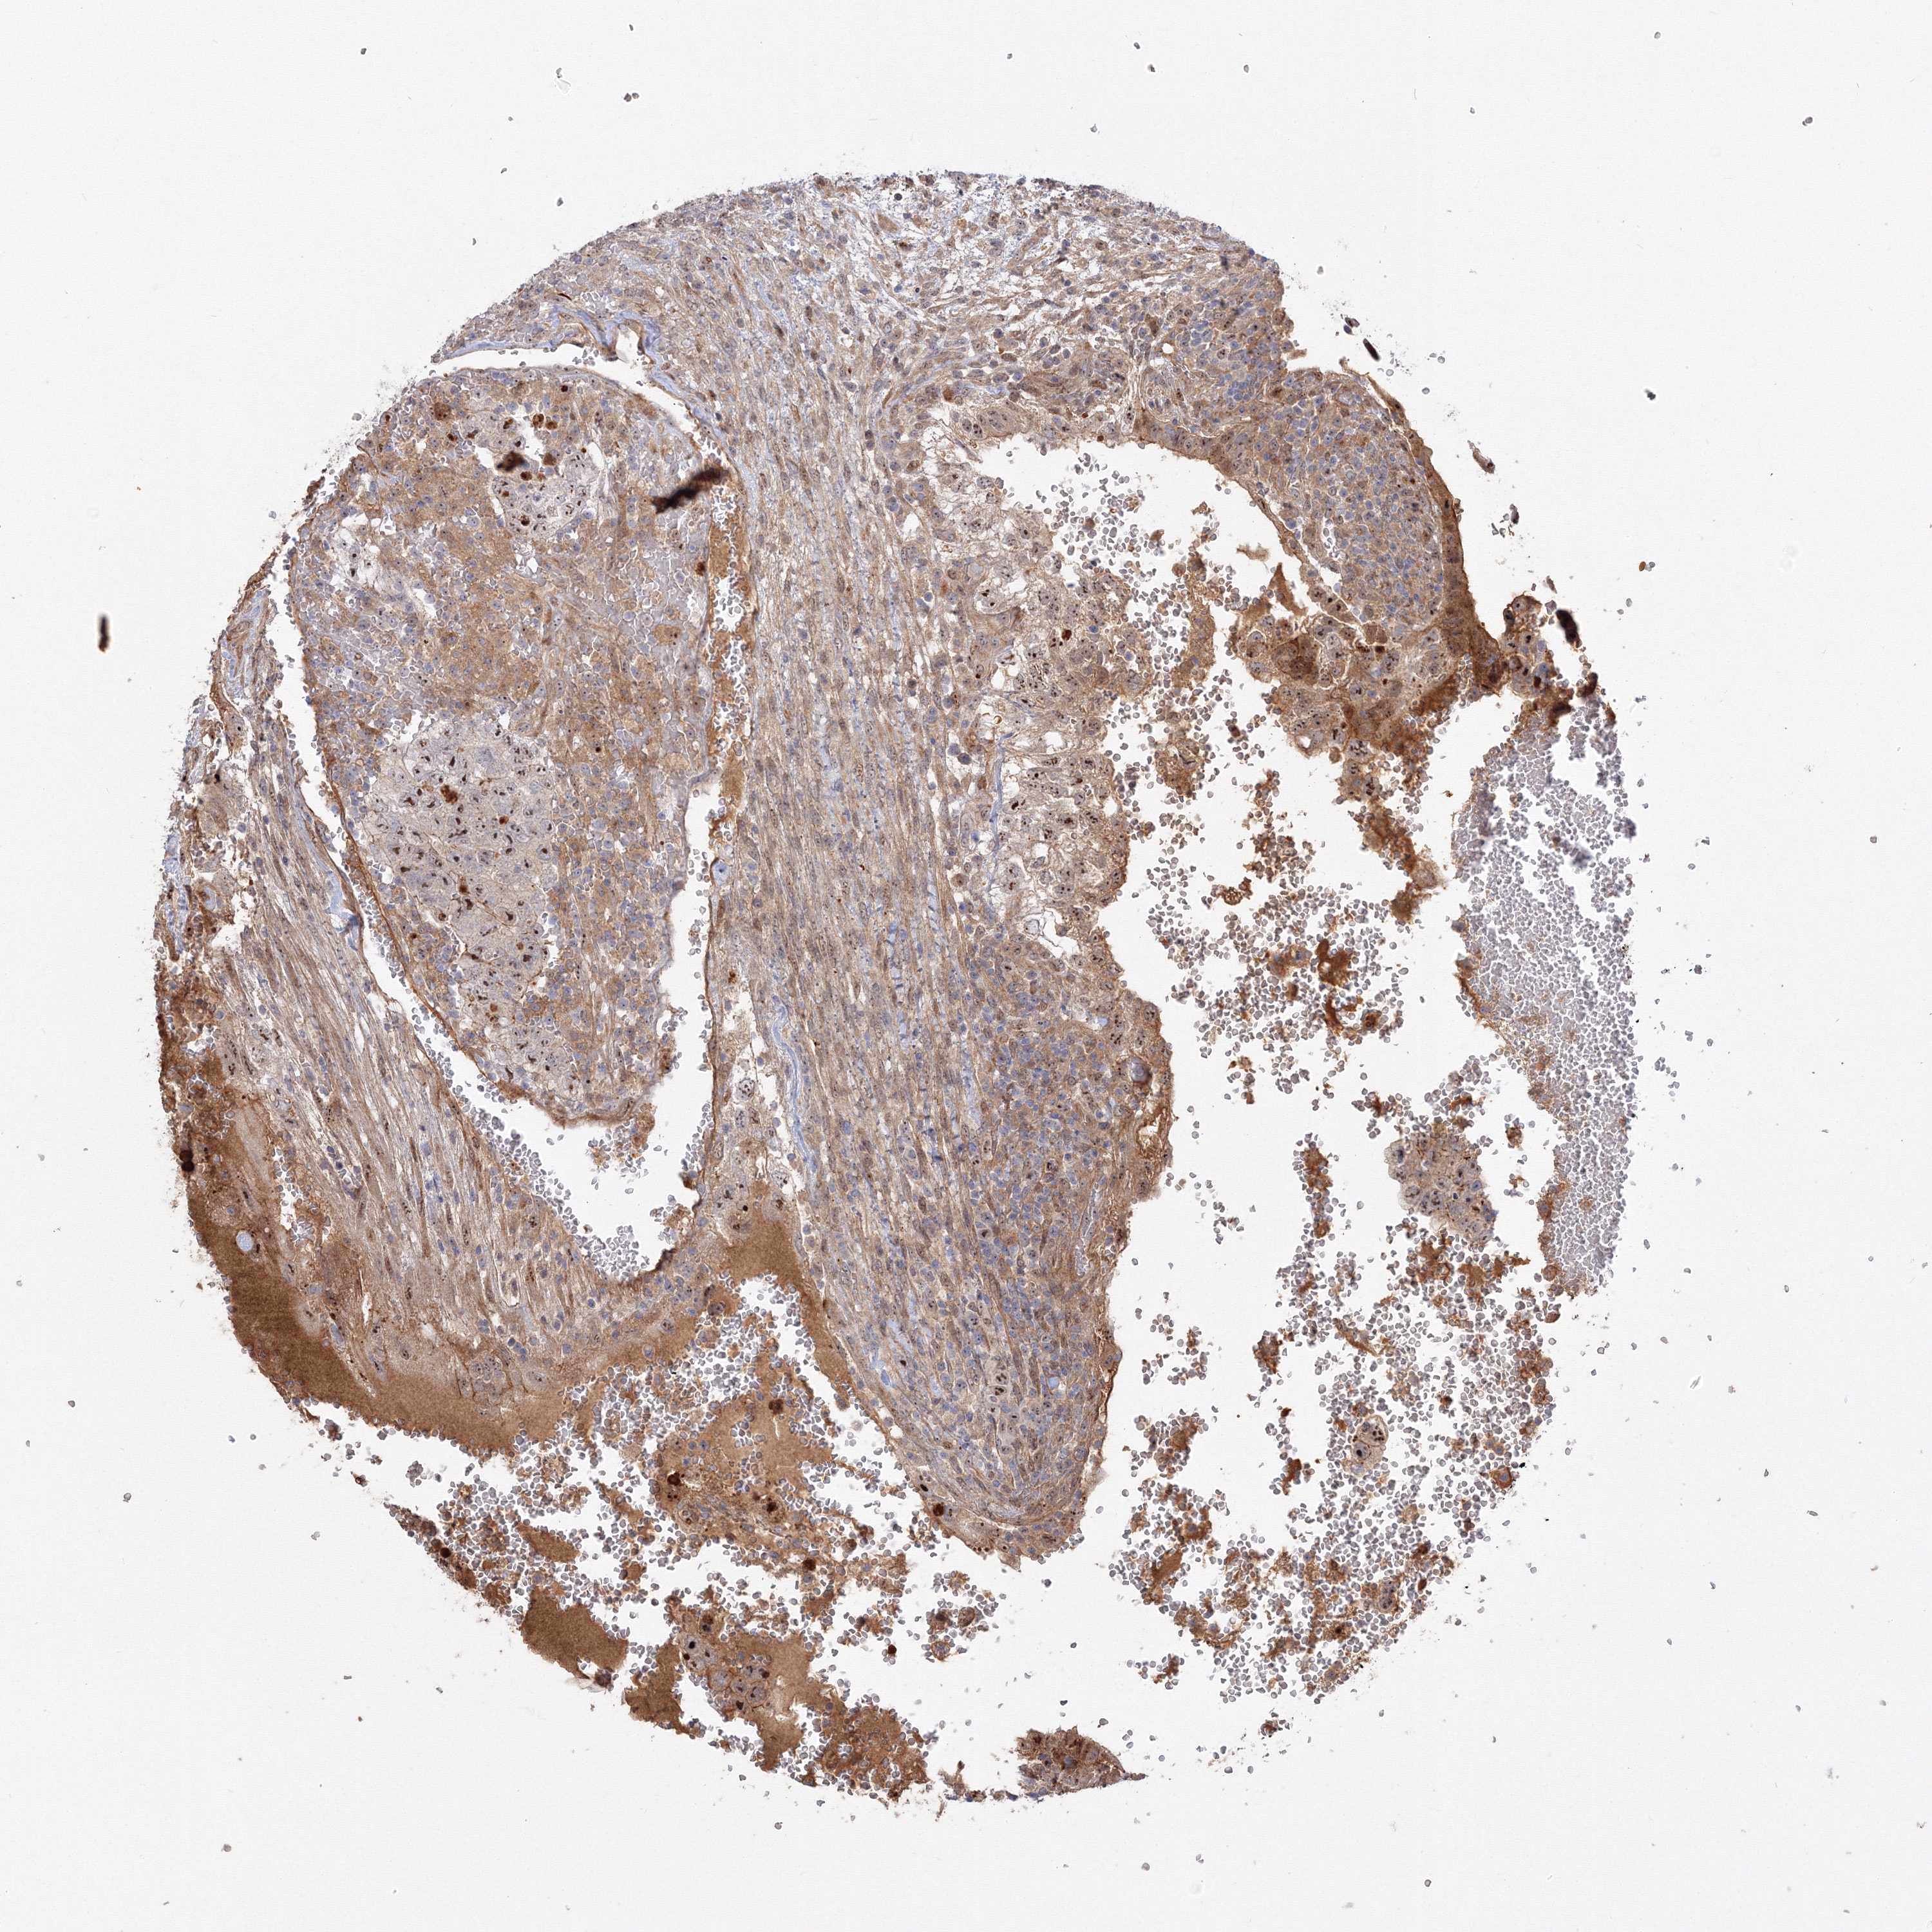

TESTIS CANCER - Protein expressioni

A mouse-over function shows sample information and annotation data. Click on an image to view it in a full screen mode. Samples can be filtered based on level of antibody staining by selecting one or several of the following categories: high, medium, low and not detected. The assay and annotation is described here.

Note that samples used for immunohistochemistry by the Human Protein Atlas do not correspond to samples in the TCGA dataset.

Antibody stainingi

Antibody staining in the annotated cell types in the current human tissue is reported as not detected, low, medium, or high, based on conventional immunohistochemistry profiling in selected tissues. This score is based on the combination of the staining intensity and fraction of stained cells.

Each image is clickable and will lead to virtual microscopy that enables deeper exploration of all samples and also displays staining intensity scores, fraction scores and subcellular localization as well as patient and tissue information for each sample.

Antibody HPA036295

Staining

High

Medium

Low

Not detected

Intensity

Strong

Moderate

Weak

Negative

Quantity

>75%

75%-25%

<25%

None

Location

Nuclear

Cytoplasmic/membranous

Cytoplasmic/membranous,nuclear

Carcinoma, Embryonal, NOS

Seminoma, NOS